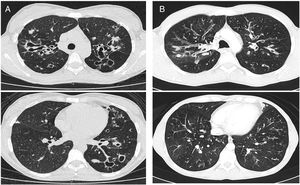

The Bhalla score evaluates the severity of bronchiectasis, peribronchial thickening, extension of bronchiectasis (number of pulmonary segments), extension of mucus plugging, sacculations and abscesses, involvement of bronchial generations, number of bullae, emphysema, and collapse/consolidation. Instead of assessing emphysema and its extension, we evaluated the extent of air trapping in the expiratory sections (Table 1). The points in each category vary from 0 to 3. The sum of the score obtained for each item was subtracted from 25 in order to obtain the overall Bhalla score. Different examples of Bhalla scores are shown in Fig. 1.7

Fig. 1.

Axial CT images of pulmonary window in different patients with CF and different Bhalla scores. Bhalla 23 is an example of a mild disease with mild bronchiectasis while Bhalla 16 presents a moderate disease with mucous plugging and bigger bronchiectasis. Finally, Bhalla 10 shows a severe disease with sacculations, greater thickness wall and higher luminal diameter of bronchiectasis, also with mucous plugging and air trapping.